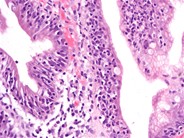

Решающим в диагностике является гистологическое ис-

следование биоптата тонкой кишки, которое выявляет рас-

ширение лимфатических сосудов в слизистом и подсли-

зистом слоях. Стенка мезентериальных лимфатических со-

судов утолщена, их мышечный слой гипертрофирован.

Лимфатические сосуды могут быть дилатированы во всех

ворсинках либо только в некоторых. Ни признаков атрофии,

ни микроорганизмов обычно не выявляют [3, 7].

Двенадцатиперстная кишка, тонкая кишка: млечные капилляры слизистой диффузно расширены и окружены небольшими количествами макрофагов, нейтрофилов, лимфоцитов и плазмоцитов. Собственная пластинка диффузно инфильтрована многочисленными плазмоцитами и лимфоцитами, а также наблюдается отек слизистой. Кишечные железы расширены, заполнены базофильным пенистым материалом и иногда содержат внутриэпителиальные лимфоциты. Поверхностный эпителий во многих очагах поврежден.

Двенадцатиперстная кишка, тонкая кишка: энтерит, лимфоплазмоцитарный, диффузный, хронический, сильный, сопровождается лимфангиэктазией слизистой.